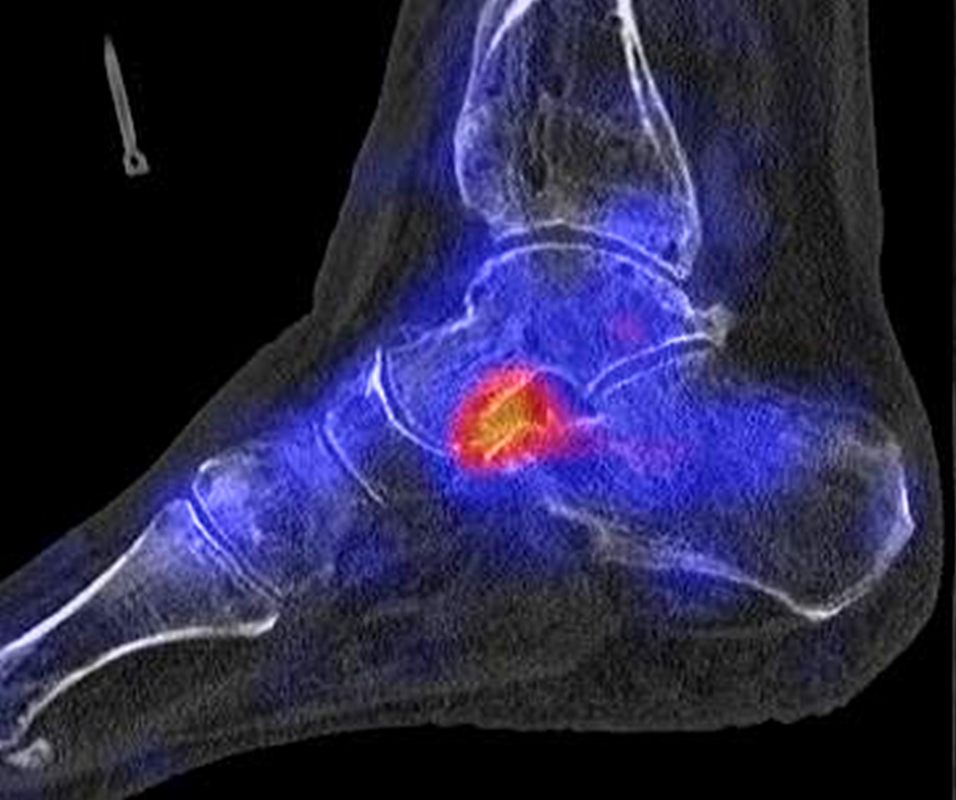

In Abbildung 3.4. ist ein typisches Beispiel für ein symptomatisches Os trigonum dargestellt.

Bei der Differenzialdiagnose von Impingement-Syndromen am Sprunggelenk kann das SPECT/CT den Ort der Symptome- verursachenden Stressreaktion darstellen 32. Eine typische Ursache für ein posteriores Impingement kann ein Os trigonum sein. Scherkräfte im Bereich der Synchondrose eines Os trigonum lösen hypermetabole Stressreaktionen aus. Die Exzision des Os trigonum stellt eine erfolgreiche Therapie dar, sodass der Befund eines szintigraphisch aktivierten Os trigonum den Erfolg einer chirurgischen Therapie vorhersagen kann 3334.